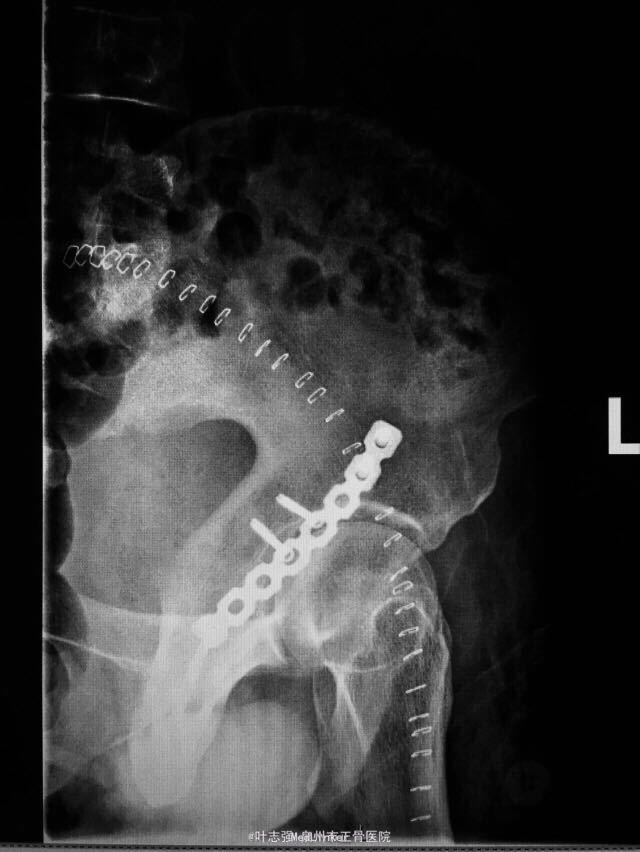

髋臼骨折伴髋关节后脱位ORIF

车祸致左髋部疼痛、活动受限1天。 53岁男性

左髋臼骨折伴髋关节后脱位 行生命支持,股骨髁上骨牵引,